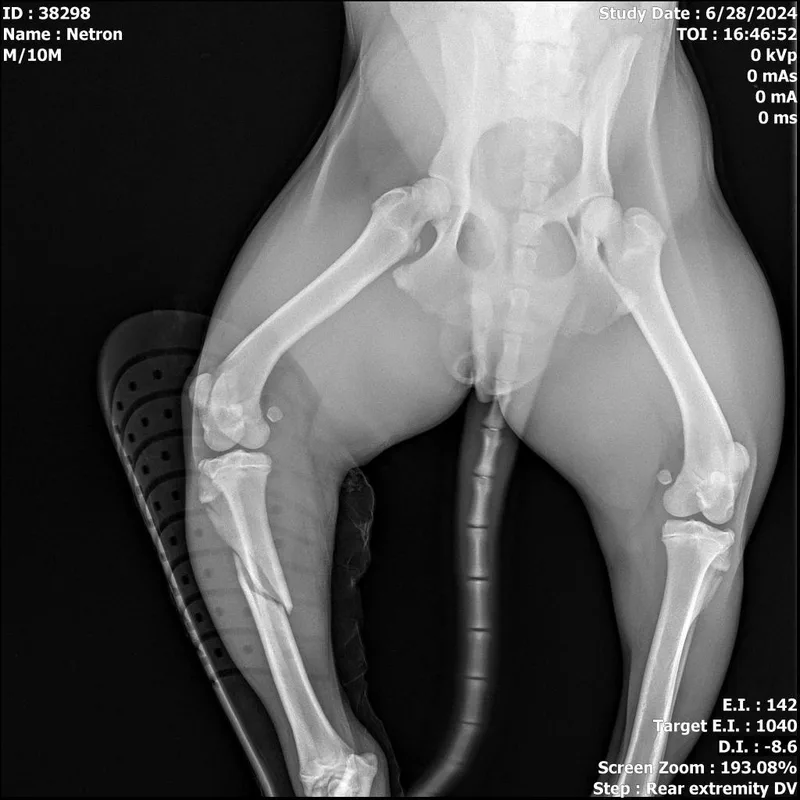

appears to have a displaced tibia fracture; this fx may be able to be set and splinted but will need to be set in alignment; x-rays have been reviewed by an off-site vet